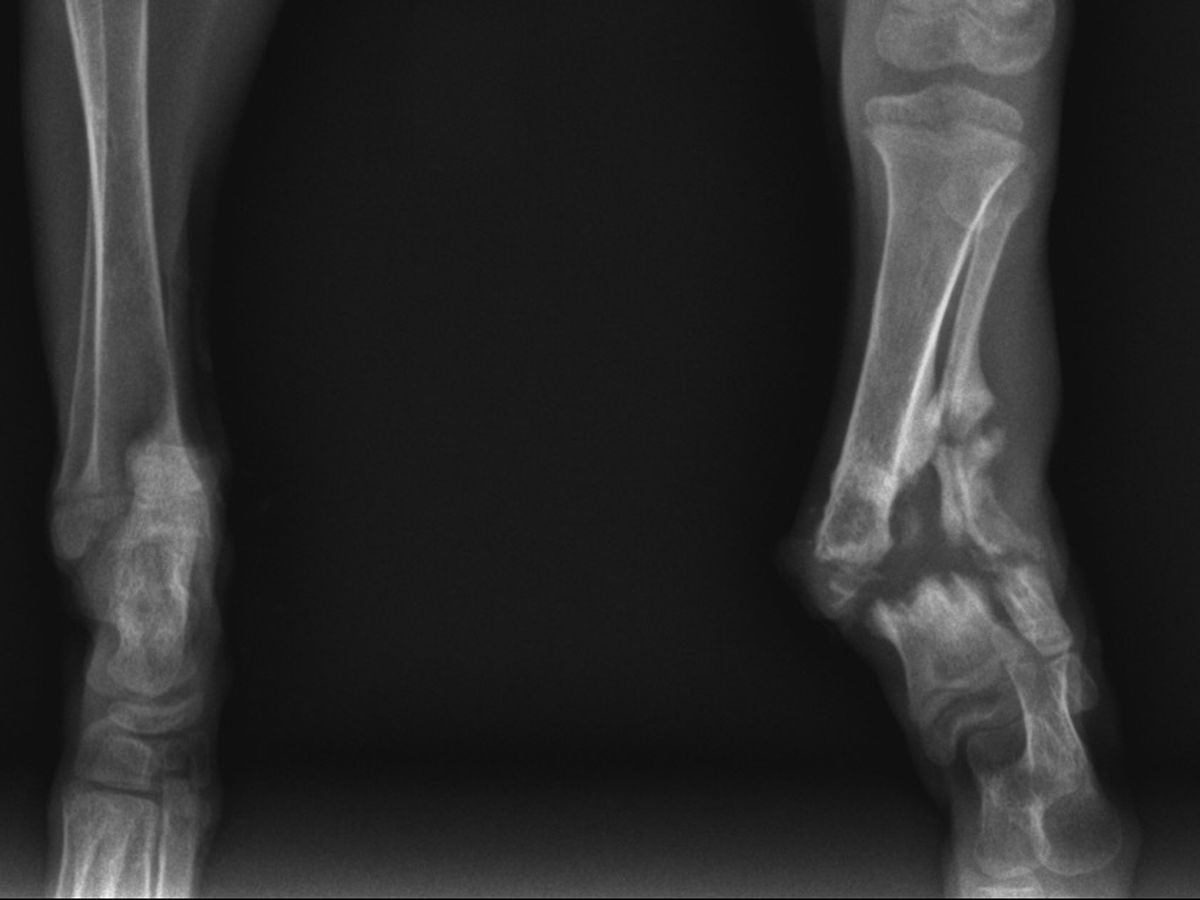

I got a text about this little guy who had been at manatee county animal services for 6 days, his stray hold was up yesterday so he was getting neutered. Someone noticed his leg looked weird and a bone was sticking out ♀️ he sat there like that for 6 days. No pain meds. They also couldn’t get X-rays. I called Dr Roses office at 4 o’clock and was like can you guys pleeeaaasssseeee squeeze this in even though you’re closing. How awesome are they that they fit him in at 4:45? He’s now on pain meds and antibiotics. Currently with Dr sabshin getting his general exam and felv/fiv test. Because we have so many amazing vets that squeeze these babies in with no notice

He has a major tibia fibula fracture that’s poking through his skin. It’s an older fracture. He’s scheduled for surgery on Monday. They’re hoping they can get a plate on with two screws in the distal portion but there may not be enough space and they may have to cross pin it and then put it in a cast for a couple weeks. As usual we are looking around the $3000-$3500 range for this repair. We do not have spare funds floating after all the recent enormous bills, so we need to raise this by Monday so he can have his much needed surgery.